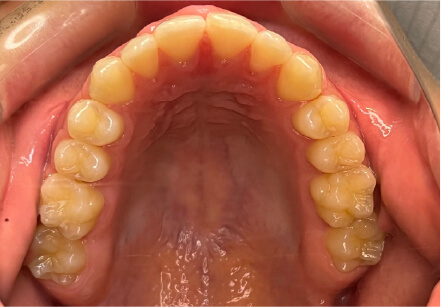

叢生の症例

17歳

/

女性

相談内容

カウンセリング・診断結果

治療内容・方法

全額アライナー矯正

術後の経過・現在の様子

クリアライナー使用

治療のリスク

痛み・歯根吸収・歯肉退縮・虫歯・後戻り

費用・治療期間

715,000円、2年10ヶ月

トレーニングなど